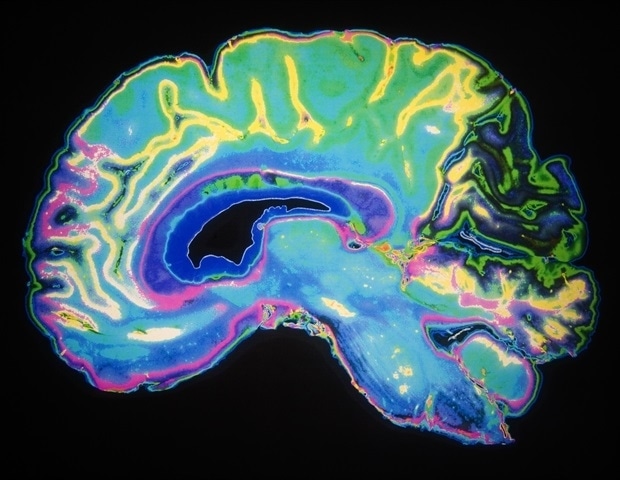

Наши мысли определяются нашими знаниями и планами, однако наше познание также может быть быстрым и гибким в обработке новой информации. Как хорошо контролируемая и в то же время очень гибкая природа познания возникает из анатомии мозга, состоящей из миллиардов нейронов и цепей? Новое исследование, проведенное исследователями из Института обучения и памяти Пикауэра при Массачусетском технологическом институте, на основе тестов на животных дает новые доказательства того, что ответом может быть теория под названием «Пространственные вычисления».

Теория пространственных вычислений, впервые предложенная в 2023 году профессором Пикауэра Эрлом К. Миллером и его коллегами Микаэлем Лундквистом и Павлом Херманом, объясняет, как нейроны в префронтальной коре могут на лету организовываться в функциональную группу, способную выполнения обработки информации, необходимой для когнитивной задачи. Более того, это позволяет нейронам участвовать в нескольких таких группах, поскольку годы экспериментов показали, что многие префронтальные нейроны действительно могут участвовать в нескольких задачах одновременно. Основная идея теории заключается в том, что мозг рекрутирует и организует специальные «оперативные группы» нейронов, используя мозговые волны «альфа» и «бета» частот (около 10-30 Гц) для подачи управляющих сигналов к физическим участкам префронтальной коры. Вместо того, чтобы перестраиваться в новые физические цепи каждый раз, когда необходимо выполнить новую задачу, нейроны в пластыре вместо этого обрабатывают информацию, следуя шаблонам возбуждения и торможения, налагаемым волнами.

«Познание — это крупномасштабная нейронная самоорганизация», — сказал Миллер, старший автор статьи в журнале Современная биология и преподаватель кафедры мозга и когнитивных наук Массачусетского технологического института. «Пространственные вычисления объясняют, как мозг это делает».